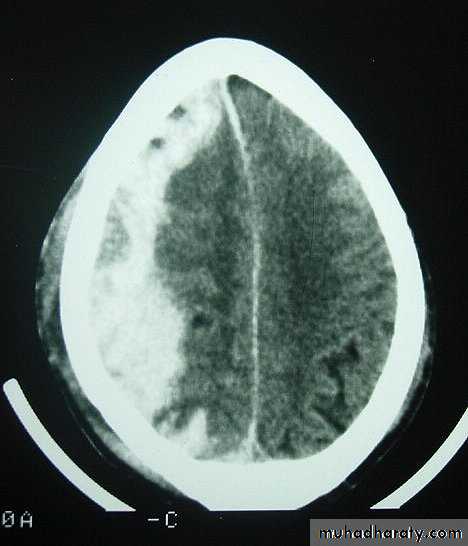

Chronic Subdural Haematoma

Most common in infants and in adults over 60 years of age secondary to SLIGHT blow to the head which may pass unnoticed.

Source of bleeding (haematoma): usually from bridging veins as they pass to the venous sinuses.

The patients present with progressive neurological deficits more than 3 weeks after the trauma.

The initial head injury is often completely forgotten.

CT scan: the acute clotted blood is initially appears white (hyperdence), but as it liquefies, it slowly becomes black (hypodense).

They should be drained if they continue to enlarge.

They are evacuated by drilling burrholes over the collection and washing it out with warmed saline.